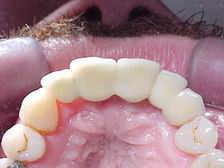

Prótese metalocerâmica personalizada VISTA OCLUSAL

Munhões personalizados sobre modelo VISTA OCLUSAL